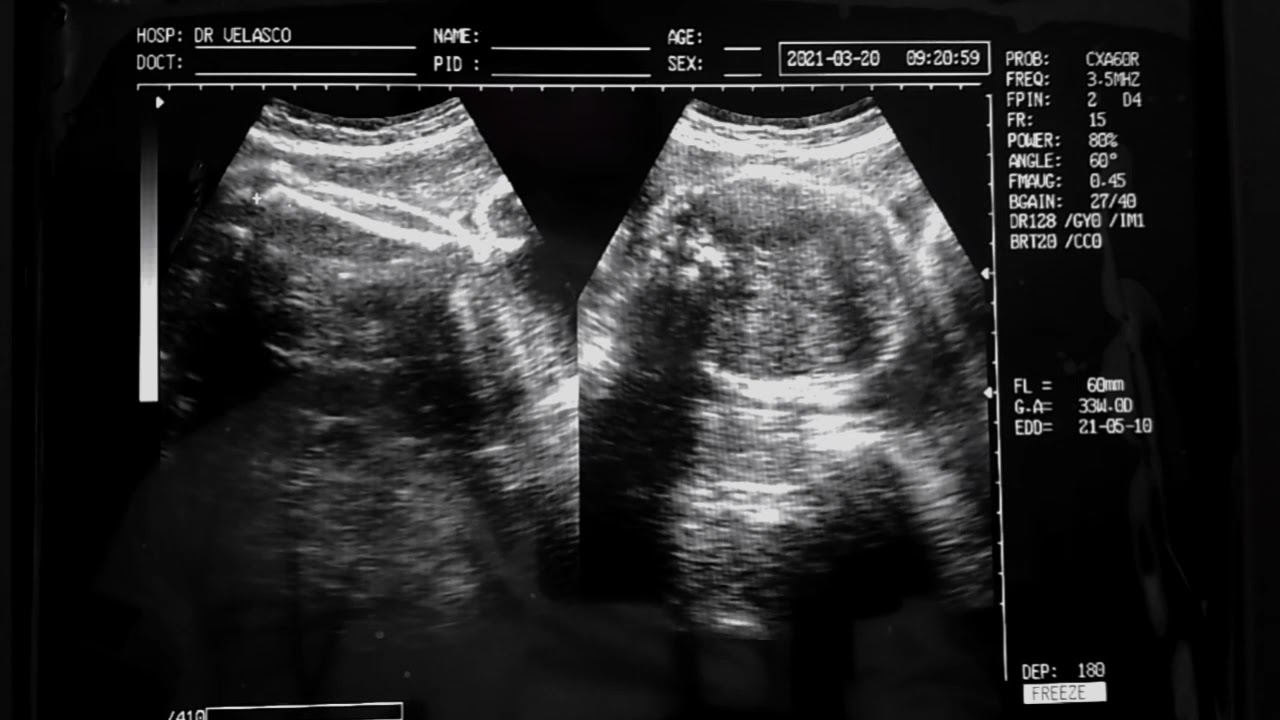

Ecografía obstétrica de 32 semanas de gestación con un feto masculino se valoram movimientos fetales así mismo se realiza fetometría.

Dr. Bernardo Velasco